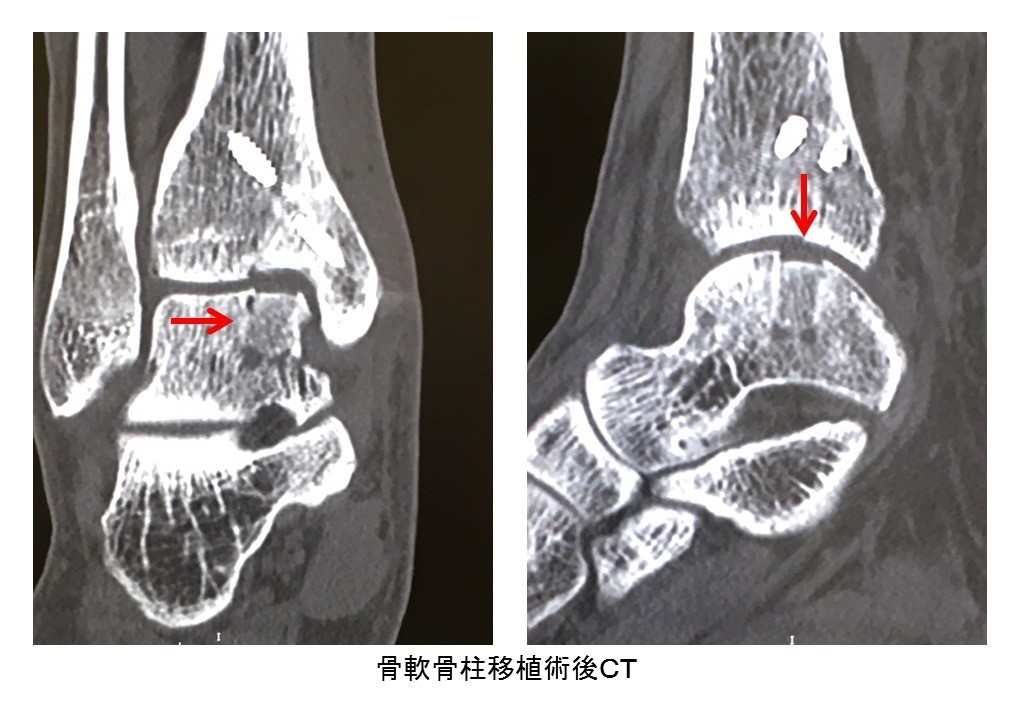

• 距骨骨軟骨損傷(離断性骨軟骨炎)

スポーツ整形

距骨骨軟骨損傷(離断性骨軟骨炎)